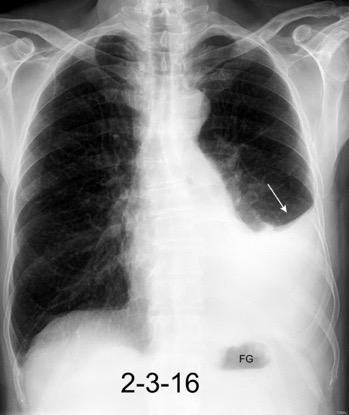

Marzo 2014: Perforación longitudinal distal secundaria a episodio de vómito (síndrome de Boerhaave). Derrame pleural izdo. que evoluciona a empiema.

Wang C-T et al. Tension hydropneumothorax in a Boerhaave syndrome patient: A case report . World J Emerg Med, 2021. Katabathina V et al. Nonvascular, nontraumatic mediastinal emergencies in adults:a comprehensive review of imaging findings. Radiographics. 2011.